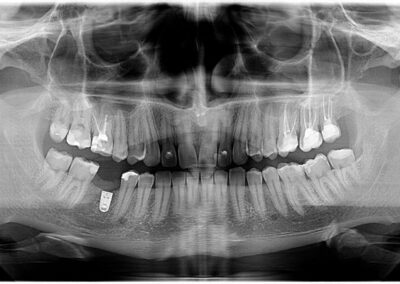

Pacijentu je nedostajao prvi molar u bočnoj regiji. Ovaj zub je posebno značajan i njegov nedostatak narušava kontinuitet celog zubnog luka. Imajući u vidu da su susedni zubi bili zdravi, kao idealno rešenje sa pacijentom je dogovorena ugradnja implanta i protetska nadoknada na implantu.

Na rendgen snimcima prikazana je donja vilica pre ugradnje implanta i donja vilica nakon perioda srastanja (oseointegracije) implanta sa koštanim tkivom.